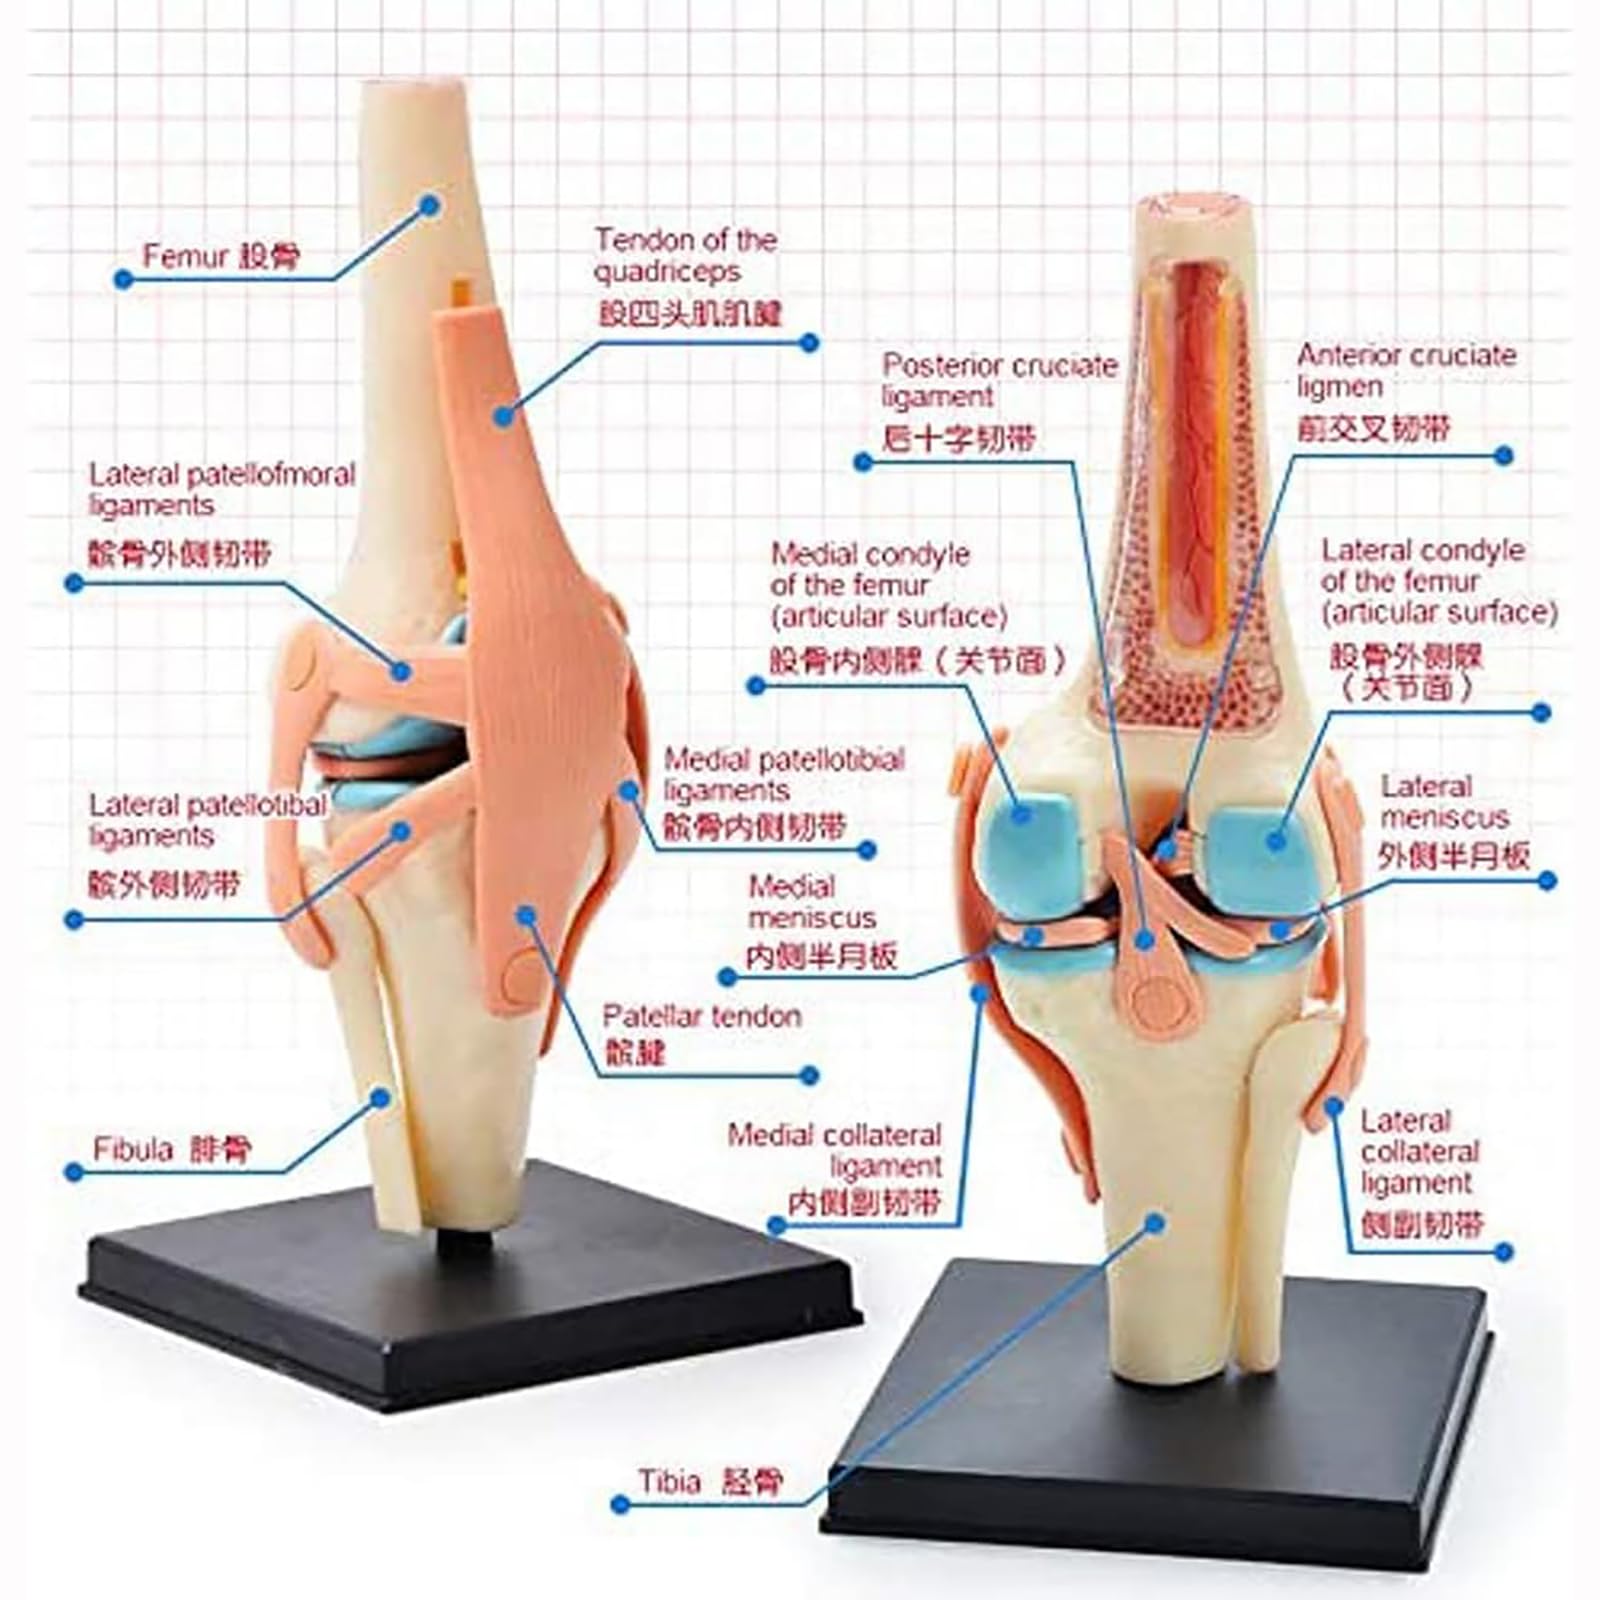

UNbit Anatomical Model of Human Knee Joint Organs 4D Model of Human Knee Articulation 23 Detachable Parts Model of Medical Teaching for Medical Education

UNbit Anatomical Model of Human Knee Joint Organs 4D Model of Human Knee Articulation 23 Detachable Parts Model of Medical Teaching for Medical Education

This anatomical model aids in the study of human biology and anatomy by providing a hands-on, 3D representation of the knee joint.